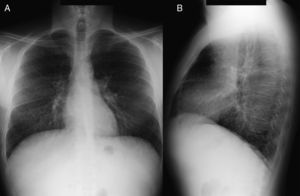

Caso clínicoPaciente varón de 40 años, diagnosticado de enfermedad de N-P con afectación hepática y pulmonar. Antecedentes personales: hepatoesplenomegalia diagnosticada desde los 6-7 meses de vida. Ingresa a los 6 años de edad por cuadro de astenia, anorexia, decaimiento y fiebre. Se le realizó radiografía de tórax posteroanterior y lateral (PA-L), en la que se apreció un patrón reticular difuso. Ante los hallazgos radiográficos y la presencia de hepatoesplenomegalia se sospechó enfermedad por depósito, realizándose biopsia de la mucosa rectal y biopsia hepática, que fueron sugestivas de enfermedad de N-P (se visualizaron macrófagos cargados de lípidos). La exploración neurológica y las pruebas de función respiratoria fueron normales. Se confirmó el diagnóstico a los 20 años mediante biopsia de piel con cultivo de fibroblastos, comprobándose un marcado déficit de actividad de esfingomielinasa ácida (ASM) característica de enfermedad N-P que, apoyando el diagnóstico clínico, sería tipo B. A los 38 años se realizó el diagnóstico molecular, en el que se observaron dos mutaciones en el gen SMPD (presentó heterocigosis en mutación p.R608del). Actualmente sigue revisiones en consultas de neumología y en consultas de hepatología, y presenta ictericia intermitente y disnea de máximos esfuerzos (grado 0 MRC). En la exploración física destaca la presencia de mínimos crepitantes bibasales, ictericia subconjuntival y hepatoesplenomegalia. La exploración neurológica es normal. En la analítica los resultados más destacables son: bilirrubina total, 4,17mg/dl; GOT, 38UI/l; GPT, 45UI/l; colesterol total, 221mg/dl. Las pruebas de función respiratoria muestran un patrón ventilatorio normal (FVC,3,84 [87,7%]; FEV1, 3,13 [86%]; FEV1/FVC, 81,58%; TLC, 5,26 [81,8%]) y una alteración leve del intercambio gaseoso (DLCO, 57,5%). Hallazgos radiográficos: radiografía PA-L de tórax (fig. 1 A-B): en el parénquima pulmonar se observa una afectación intersticial reticular difusa de predominio en campos medios e inferiores; TCAR (Aquilion Toshiba de 64 detectores) (fig. 2 A y B): afectación en vidrio deslustrado difusa aunque de predominio en los lóbulos inferiores con engrosamientos septales subpleurales en la pleura periférica, mediastínica y cisuras. No se observan adenopatías mediastínicas ni hiliares. El paciente actualmente no sigue ningún tratamiento y únicamente presenta afectación hepática y pulmonar sin que haya afectación del sistema nervioso central.